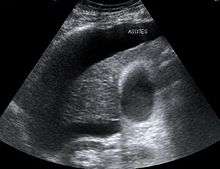

![]() Liver pathology is altered in HRS while kidney histology is normal. The upper image is a trichrome stain of cirrhosis of the liver, the most common cause of HRS. The lower image is a PAS stain of normal kidney histology. | |